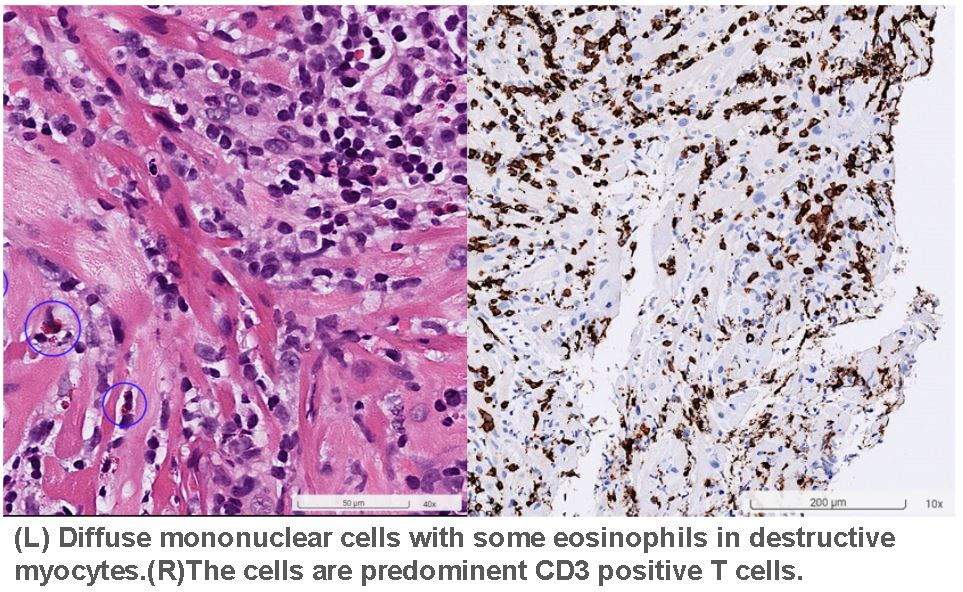

Pathology:

Diffuse mononuclear cells with some eosinophils in destructive myocytes.The cells are predominent CD3 positive T cells. Viral myocarditis isfavored.

**STEP2: Endomyocardial Biopsy**Puncturedright EIV; placed 7Fr sheath.Advancedlong sheath with 6Fr pigtail for RV angiography, localized atmid-septum. Collected 4 biopsy specimens (1 mm³ each) forhistopathology.

**STEP2: Endomyocardial Biopsy**Puncturedright EIV; placed 7Fr sheath.Advancedlong sheath with 6Fr pigtail for RV angiography, localized atmid-septum. Collected 4 biopsy specimens (1 mm³ each) forhistopathology.